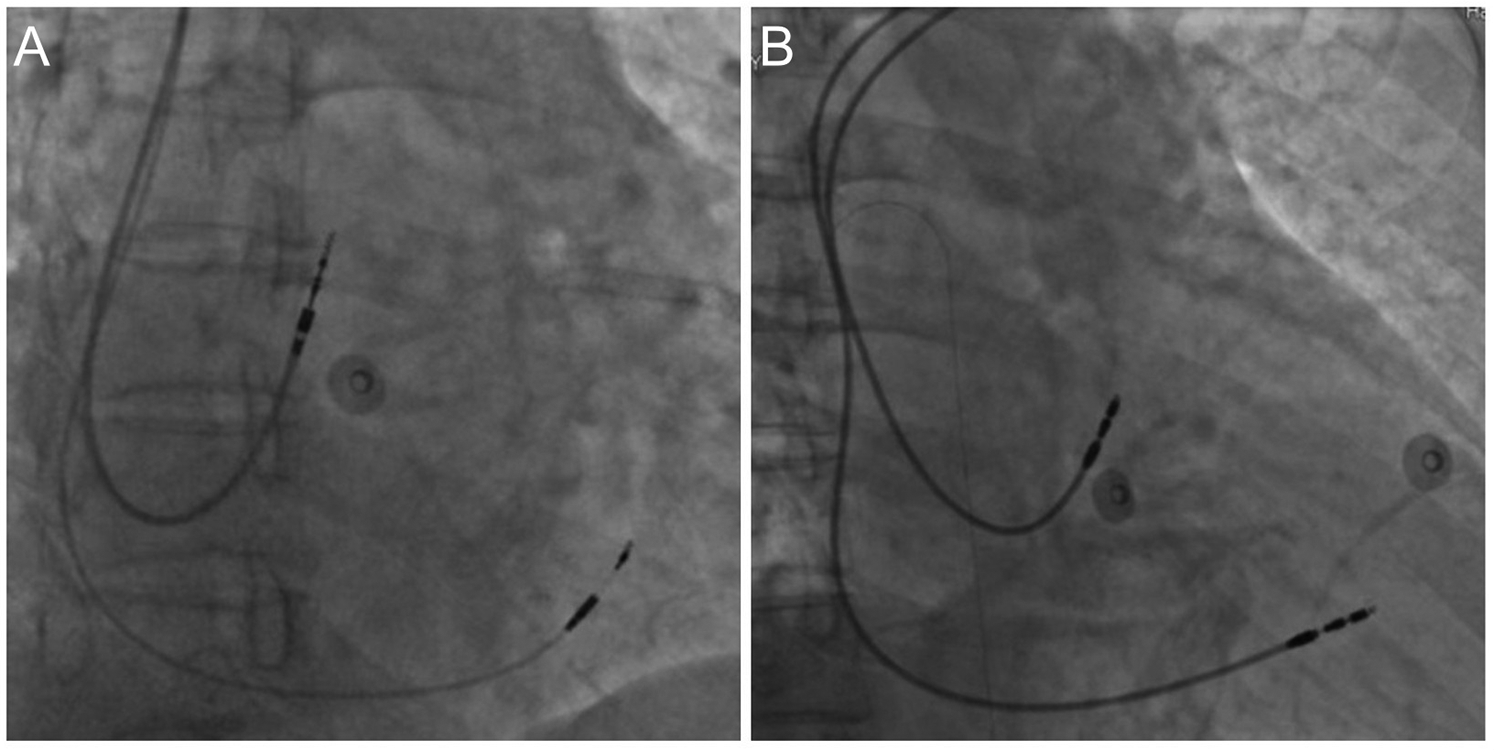

For the left bundle branch pacing (LBBP) group, a C315 HIS delivery sheath is introduced along the guide wire. Right ventriculography is performed to display the tricuspid valve. The electrode is then introduced through the sheath, mapping the His bundle. The electrode is advanced and rotated to locate the proximal LBB. Multiple lead physiological recordings are taken to verify the detection of the LBB potential, the pacing electrode tip, and confirm the pacing pattern indicative of right bundle branch block. Additionally, the recordings are used to ensure that the pacing area is specific to LBBP only and not left ventricular septal pacing. Peak time is measured, and parameters such as ventricular sensing, impedance, and bundle branch threshold are tested. If necessary, a dual lead configuration is employed to find the optimal pacing modalities. After successful implantation, the second electrode is retracted to the atrium and positioned at the top of the atrial septum (Figure 1A). In most cases, the right atrial electrode is placed in the right atrial appendage, with only a few cases requiring placement at the atrial septum due to complications.

Figure 1

Dual-Chamber pacemaker implantation. (A) Left bundle branch pacing; (B) right ventricular septal pacing.

For the right ventricular septal pacing (RVSP) group, an 8F tear-open sheath is introduced along the guide wire. The right atrium and right ventricular electrodes are introduced through the sheath. The right atrial electrode is secured to the top of the atrial septum, and the right ventricular electrode is fixed to the mid-septum. After electrode placement, testing includes atrial sensing, impedance, and threshold. Pacing the atrium ensures no diaphragmatic contractions. The pulse generator is then connected and placed in the pocket. The electrocardiogram confirms the pacemaker's normal operation (Figure 1B).